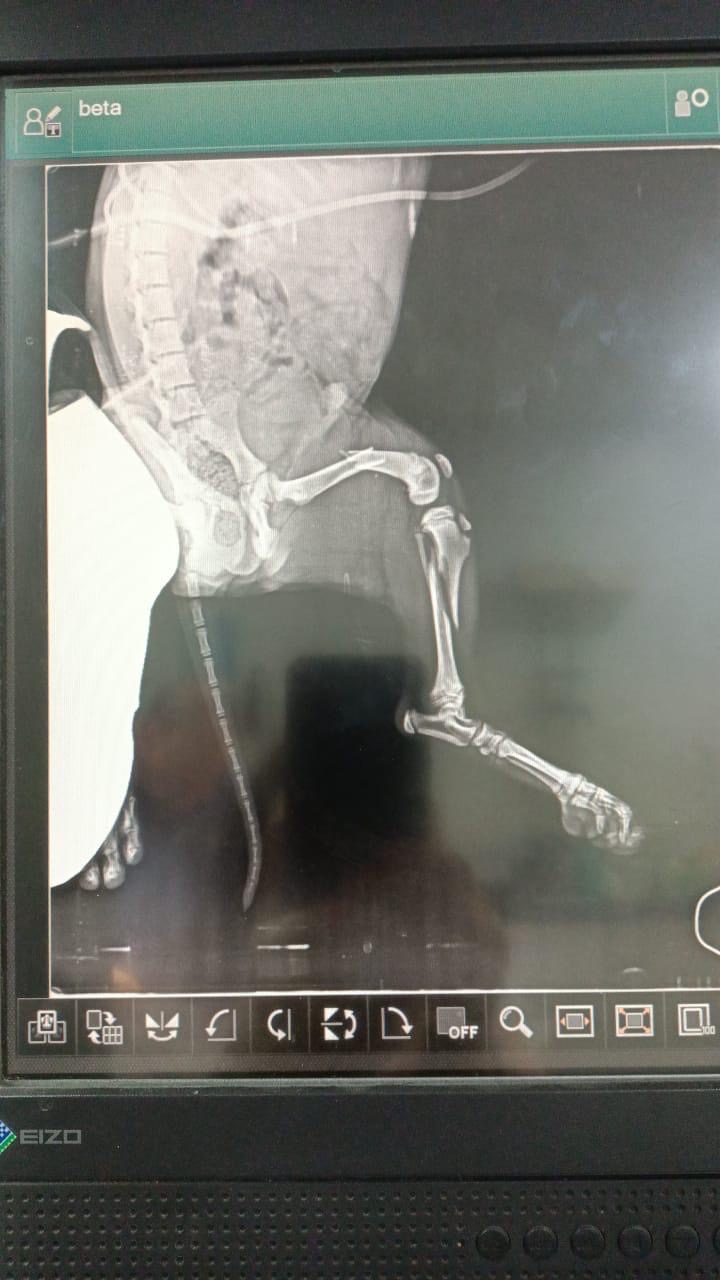

LANDON a été trouvé chiot et blessé sur la route (patte cassée), au Liban. Recueilli et soigné par le Refuge de l’association BETA LEBANON.